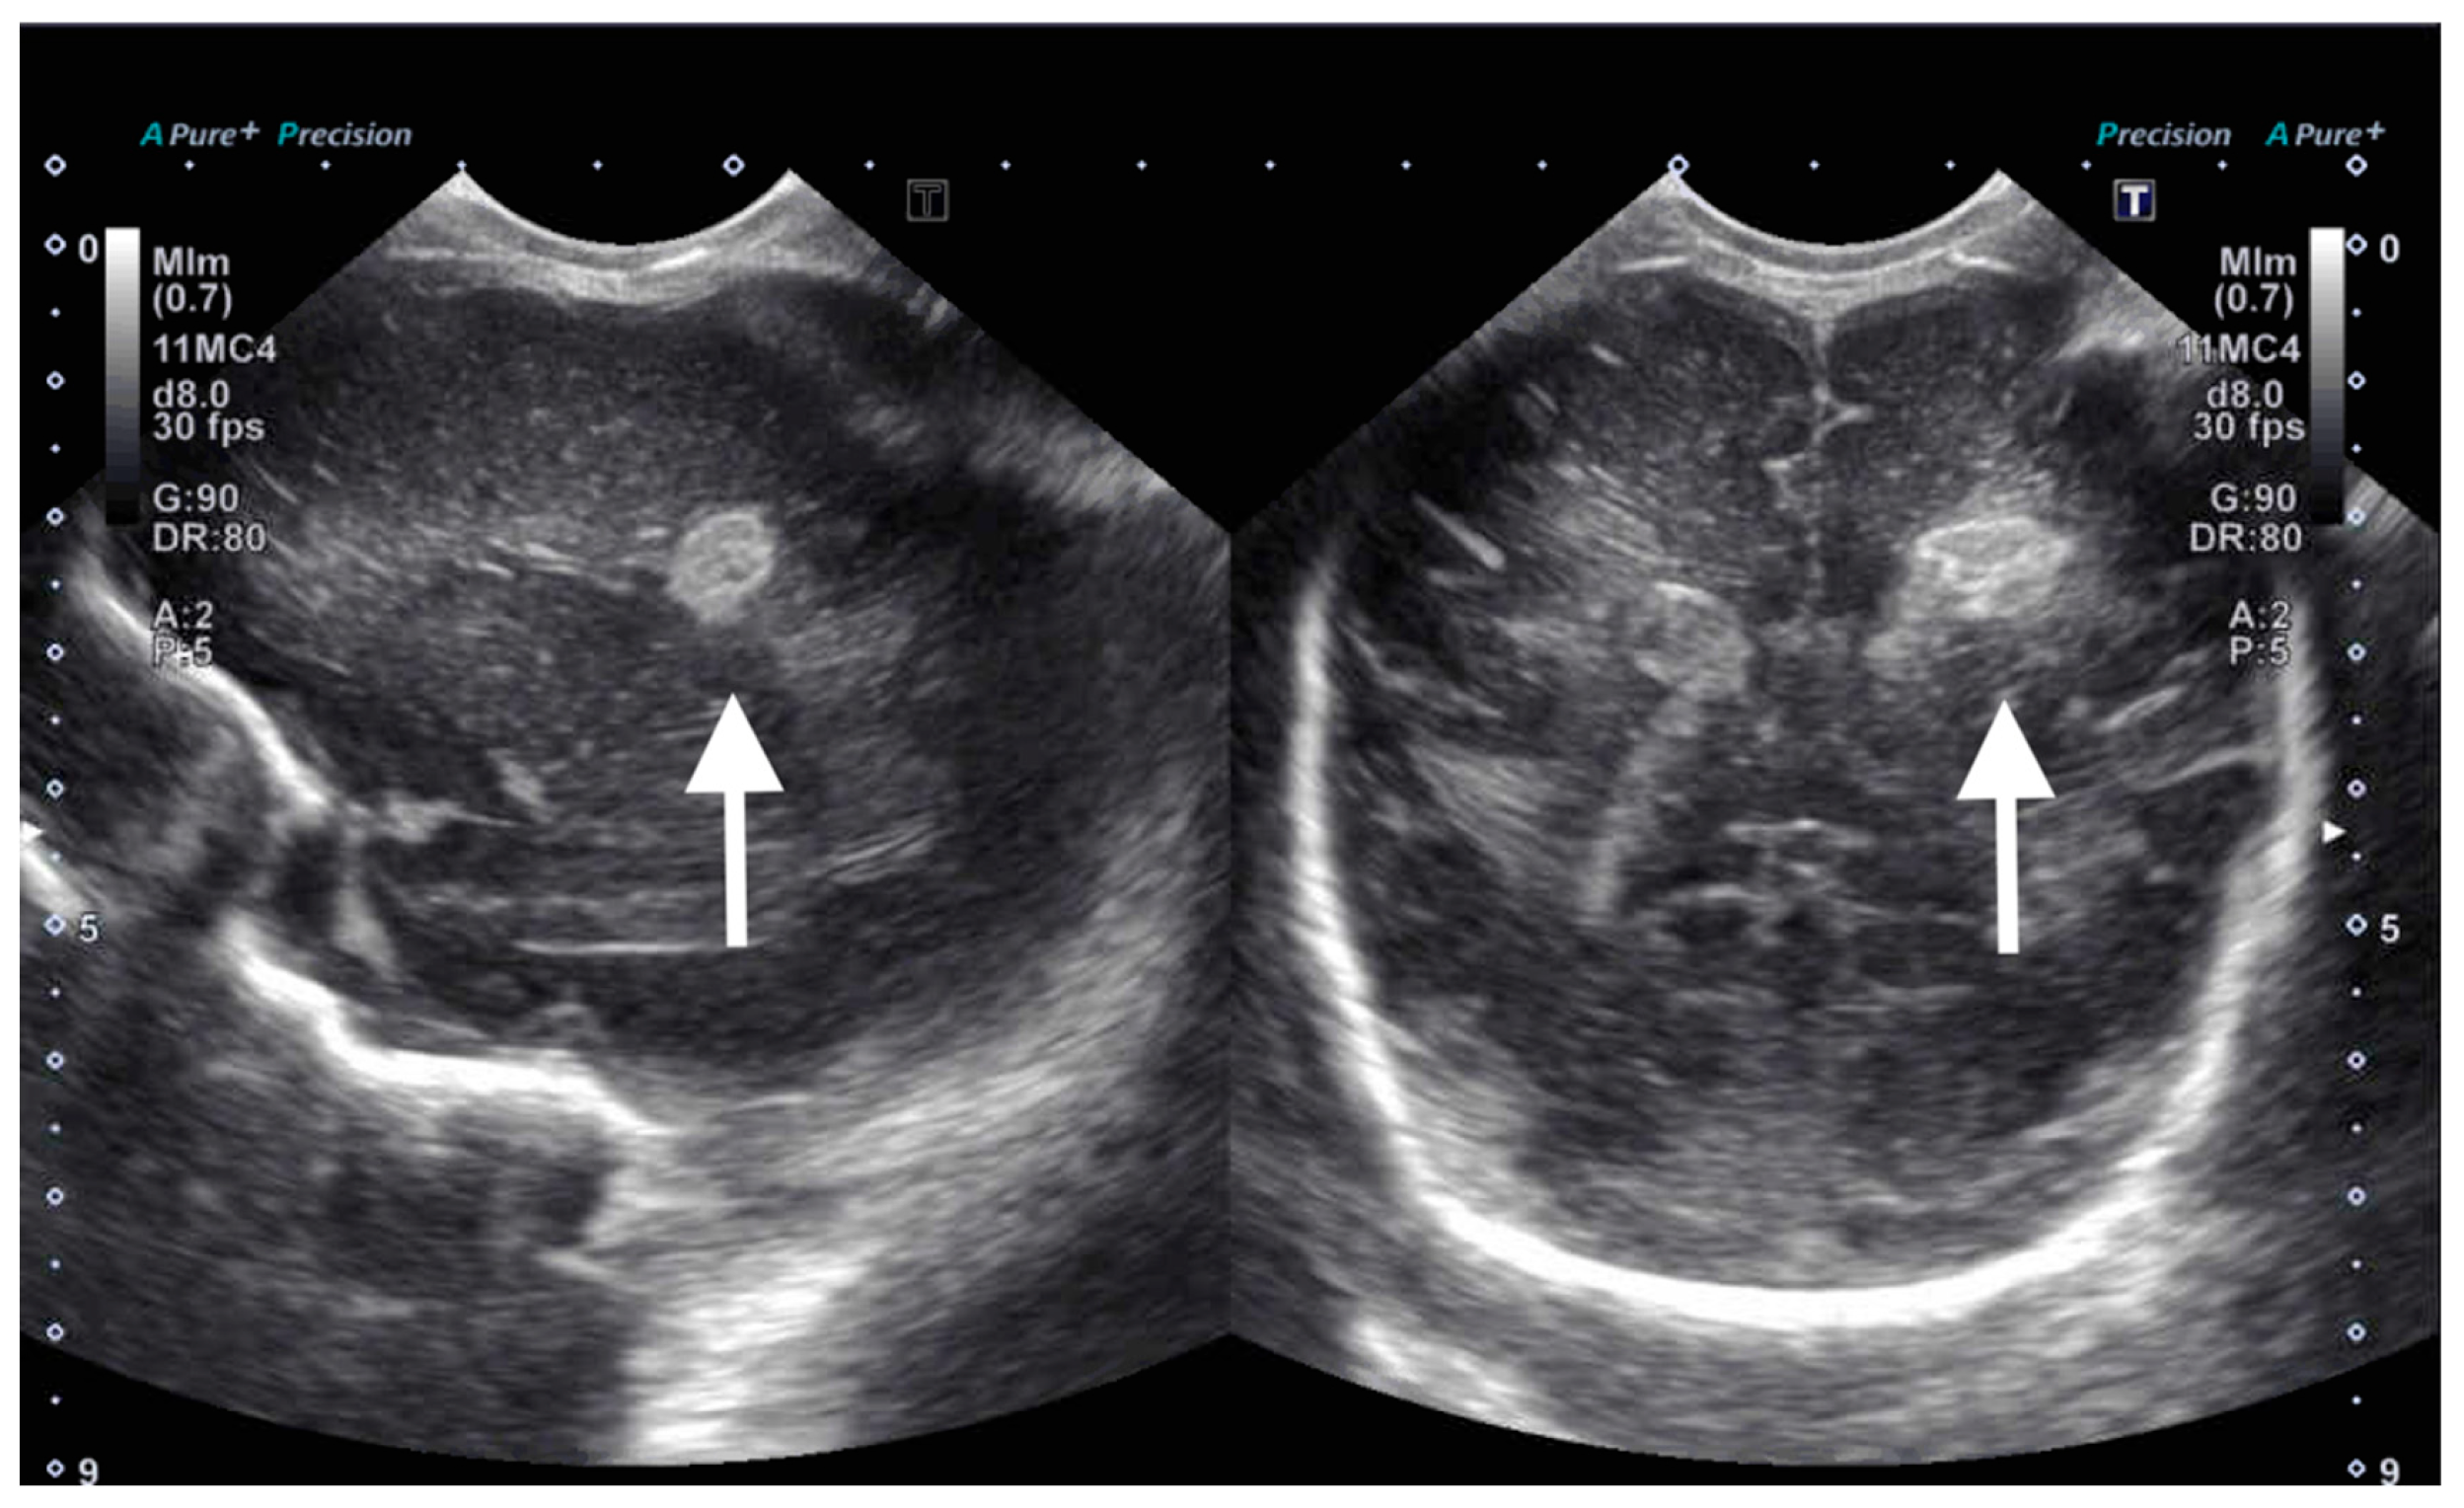

On DOL 5, the patient developed worsening abdominal distention with increased free fluid, rising lactate level, and continued oliguria with minimal brown-colored output, indicating potential bladder rupture. Renal ultrasound at that time demonstrated structurally normal kidneys and ureters, with contusive injuries in the parenchyma (Figure 1 and Figure 2). Pediatric urology was consulted. Diagnostic paracenteses and non-voiding cystogram showed no urinary leak. Computed tomography (CT) of the abdomen and pelvis was performed to further evaluate for free fluid or perforated viscus showed no renal contusion, but noted both kidneys had patchy opacification in the capsule and medulla, consistent with bilateral renal cortical necrosis (Figure 3). Cranial ultrasound was also performed at this time and showed focal parenchymal hemorrhage in the posterior portion of the left frontal lobe (Figure 4).

Figure 2.

Ultrasound of left kidney on day of life 5 showing increased focal echogenicity of the upper and lower poles (arrows).